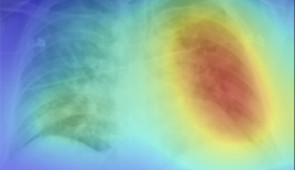

Heat maps

Grad-CAM heat maps of feature importance for positive COVID-19 prediction. Credit: Northwestern University